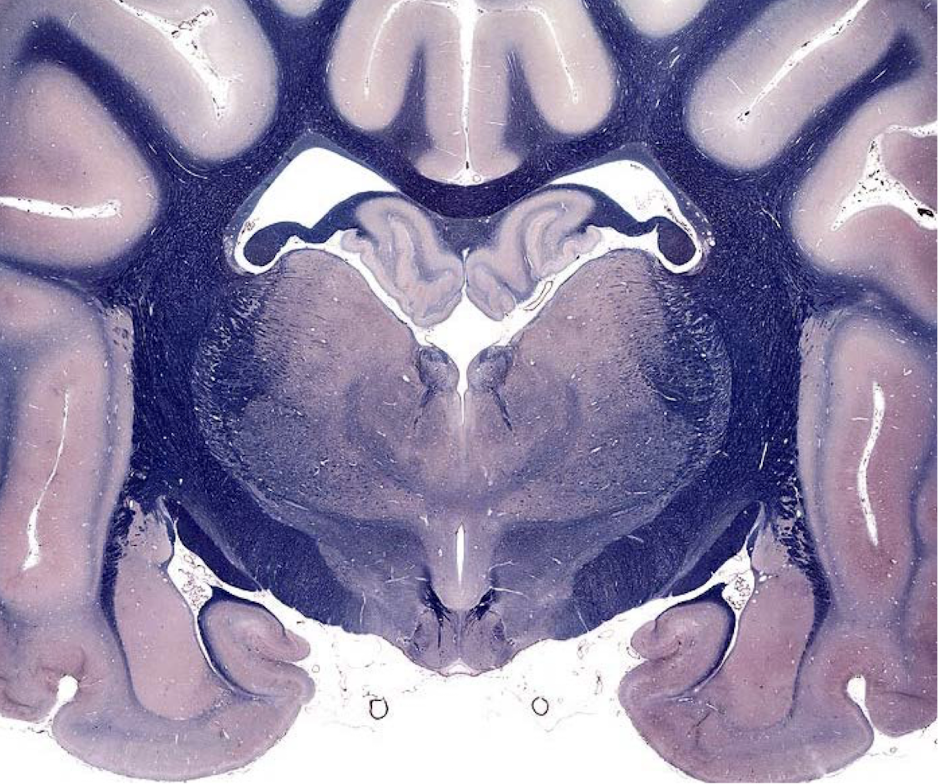

what section of the brain is shown?

middle medulla

- open 4th ventricle

- no trapezoid body

- no olivary nuclei

- pyramids (indicates medulla)